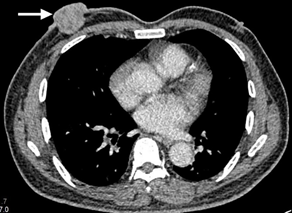

Figure 4 CT scan image sagittal view showing extension of the lesion into the thoracic cavity.